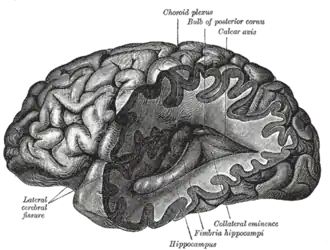

Noradrenaline system

The noradrenaline system consists of around 15,000 neurons, primarily in the locus coeruleus.[12] This is diminutive compared to the more than 100 billion neurons in the brain. As with dopaminergic neurons in the substantia nigra, neurons in the locus coeruleus tend to be melanin-pigmented. Noradrenaline is released from the neurons, and acts on adrenergic receptors. Noradrenaline is often released steadily so that it can prepare the supporting glial cells for calibrated responses. Despite containing a relatively small number of neurons, when activated, the noradrenaline system plays major roles in the brain including involvement in suppression of the neuroinflammatory response, stimulation of neuronal plasticity through LTP, regulation of glutamate uptake by astrocytes and LTD, and consolidation of memory.[13]

Dopamine system

The dopamine or dopaminergic system consists of several pathways, originating from the ventral tegmentum or substantia nigra as examples. It acts on dopamine receptors.[14]

Cholinergic system

The cholinergic system consists of projection neurons from the pedunculopontine nucleus, laterodorsal tegmental nucleus, and basal forebrain and interneurons from the striatum and nucleus accumbens. It is not yet clear whether acetylcholine as a neuromodulator acts through volume transmission or classical synaptic transmission, as there is evidence to support both theories. Acetylcholine binds to both metabotropic muscarinic receptors (mAChR) and the ionotropic nicotinic receptors (nAChR). The cholinergic system has been found to be involved in responding to cues related to the reward pathway, enhancing signal detection and sensory attention, regulating homeostasis, mediating the stress response, and encoding the formation of memories.[23][24]